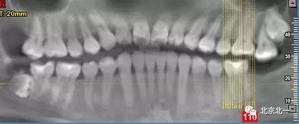

圖七:去骨后看不見牙齒位置方向。顏色無法區(qū)分,拍片確認(rèn)一下剛才去骨的以及截的冠就是智齒。

圖八:把牙根優(yōu)先取出后還是看不見牙冠在哪里,實(shí)在貼的神經(jīng)管太近, 只能再次拍一個(gè)cbct確認(rèn)。

圖九:重建后可見牙冠位于第二磨牙遠(yuǎn)中,舌側(cè)傾斜。